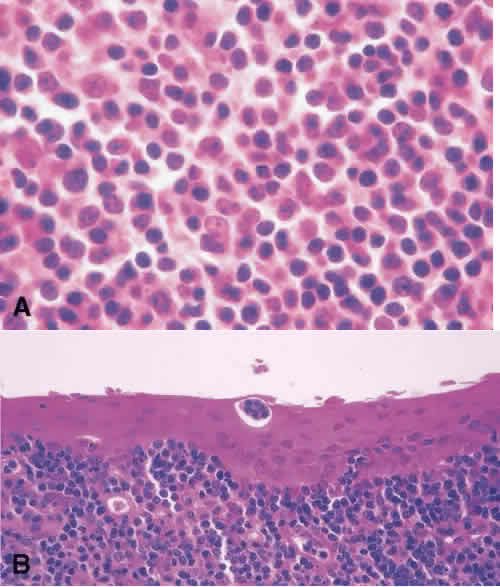

Lymphoid Lesions of the Conjunctiva Benign and malignant lymphoid proliferation may present clinically as a relatively flat lesion with a smooth surface and salmon pink appearance.84 Tissue biopsy is necessary to categorize them because there is a spectrum of lymphoproliferative lesions that can occur in the conjunctiva. They can be benign as reactive lymphoid hyperplasia or malignant as non-Hodgkin lymphoma. Hodgkin lymphoma of the conjunctiva is rare. Marginal zone B-cell lymphoma is the most common type in the conjunctiva. Lymphomas occurring in the conjunctiva have a relatively good prognosis. Systemic lymphoma can develop concurrently with reactive lymphoid hyperplasia (25% of cases) or malignant lymphoma (50%–75% of cases).84 Ancillary tests are recommended in classifying benign versus malignant lymphoproliferative lesions. Immunophenotyping with flow cytometry or immunoperoxidase staining may show monoclonality. A monoclonal lesion is suggestive of a malignant process. However, a benign lesion can harbor a clone, and the results of flow cytometry should be interpreted in light of the histology.85Histologically, reactive lymphoid hyperplasia is characterized by the presence of reactive endothelial cells, follicular centers with mitotic figures limited to the follicle. Tingible body macrophages may also be present (Fig. 15). In marginal zone B-cell lymphoma, the follicles are atretic, and tingible body macrophages are absent. The lymphoid tumor cells can be present in the conjunctival epithelium and are characterized as lymphoepithelial lesions(Fig. 16). |